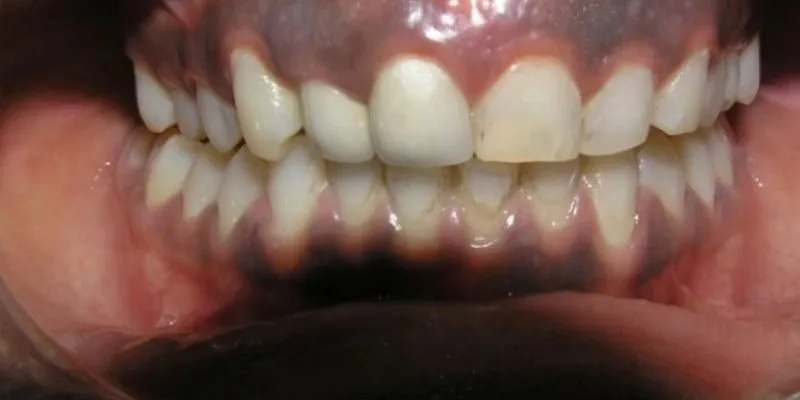

1. Biểu hiện tại răng miệng và tay chân:

Răng có thể bị đen xỉn hoặc xuất hiện các vệt đen.